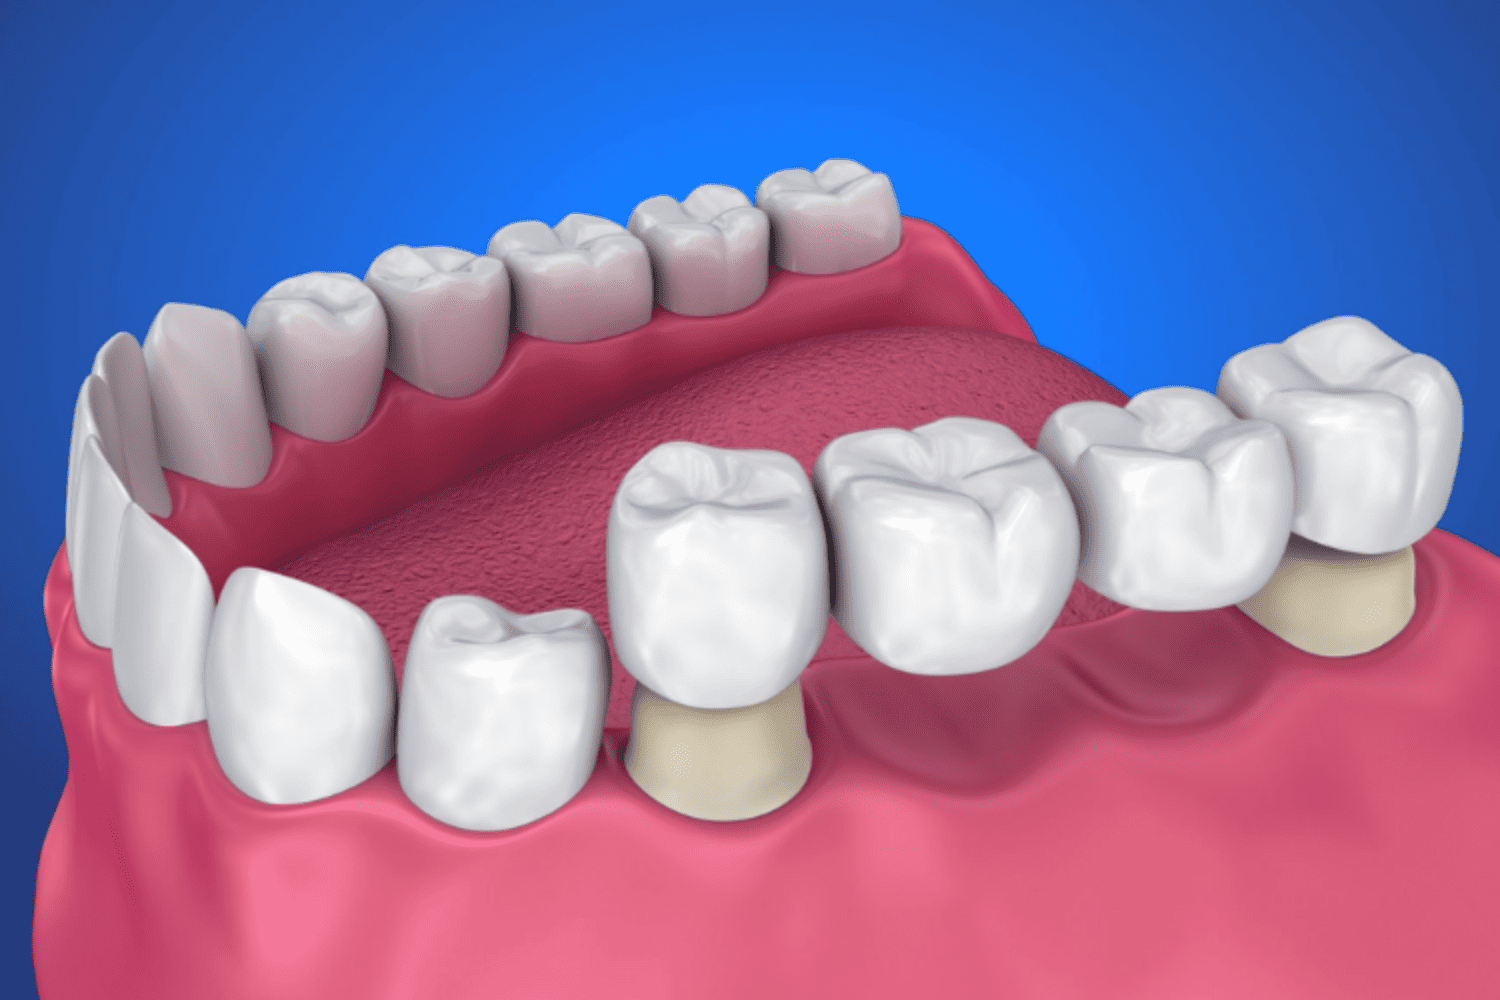

Dental Crowns in Jaipur Services Crowns Bridges Dentures...